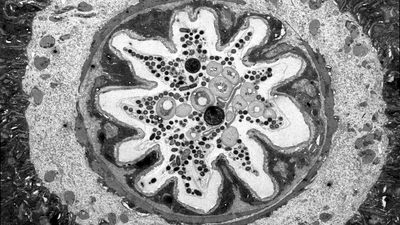

caption test